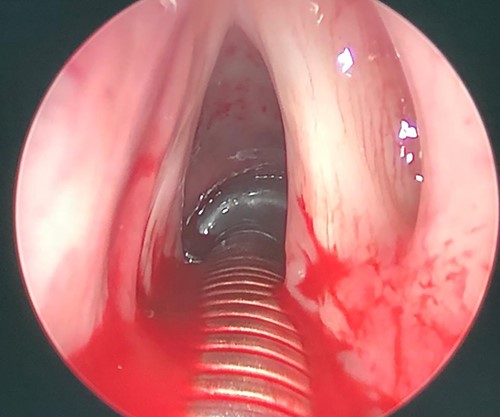

Intraoperative picture, showing left sided mass originated from left false vocal fold.

Patient was booked for direct laryngobronchoscopy with left false vocal cord mass excisional biopsy using Co2 laser. Examination under general anesthesia showed the mass extending from the left false vocal cord to the left ventricle (Figs 3 and 4). It measured 2 × 0.5 × 1 cm. The subglottic area was patent with no masses seen (Fig. 5). The mass was excised completely using Co2 laser aiding in patent airway (Fig. 6). Specimen was sent for histopathology.